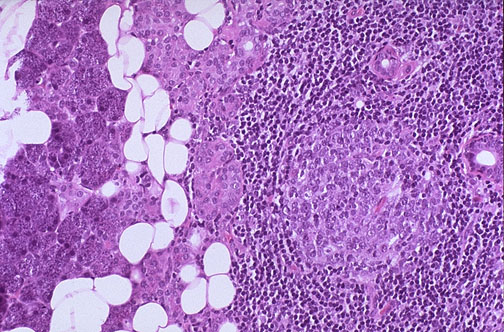

The enlarged parotid gland seen here at low power has extensive lymphoid infiltrates and even a germinal center just left of center. Such an intense mononuclear infiltrate could be seen early in Sjogren's syndrome, an autoimmune disease that involves salivary glands (with xerostomia) and lacrimal glands (with xerophthalmia). |